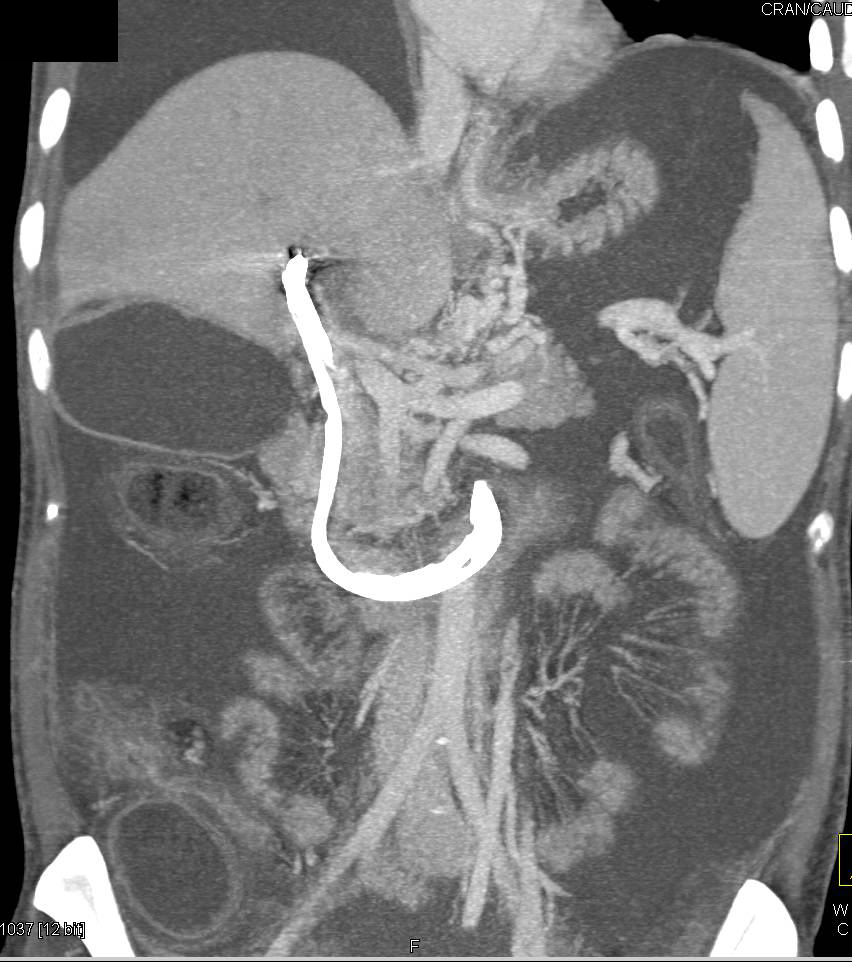

Hepatocellular Carcinoma (Hepatoma) with Neovascularity Arising in a Cirrhotic Liver. Arteriovenous (AV) Shunting Also Seen